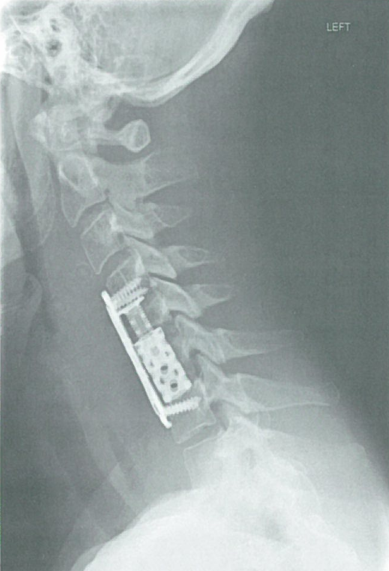

图2 在下颈椎VBR钛笼联合应用前路钛板。C5-6椎体切除术后,植入VBR钛笼,前方C4至C7钛板固定。